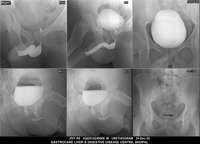

Section: URETHROGRAM Total: 95 images